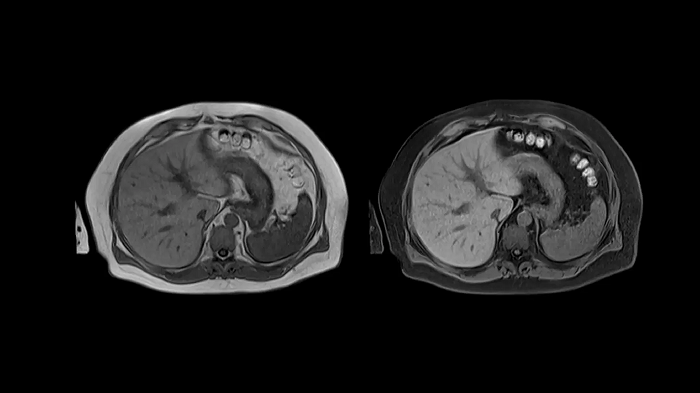

Abdomen

T1 VIBE Dixon with CAIPIRINHA

Benefit from Siemens Healthineers’ dedicated CAIPIRINHA acceleration to gain a complete abdominal volume within a single breath-hold. The Dixon technique offers outstanding fat-water separation for a flawless representation of the abdominal anatomy.

• Contour L Coil

• Spine Coil

80 cm bore MAGNETOM Free.Max

Image Courtesy: University Hospital Erlangen, Germany | Image-ID: 4aaaa0458